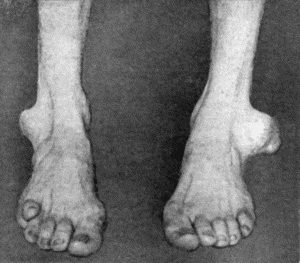

| 164. | Charcot's Disease of both Ankles: front view | 535 |

| 165. | Charcot's Disease of both Ankles: back view | 536 |